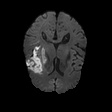

We conducted experiments on four brain imaging datasets: BraTS2017, BraTS2018, BraTS2019, and ISLES2022 [33, 34, 35, 36]. The BraTS datasets, developed for the MICCAI brain tumor segmentation challenge, contain 285, 285, and 335 labeled cases respectively, categorized into high-grade and low-grade gliomas. Each case includes 3D MRI scans from four modalities (T1, T2, FLAIR, T1c); we primarily used FLAIR. Preprocessing involved brain region cropping and intensity normalization. Dataset splits were 200/25/60 as train/val/test for BraTS2017 and BraTS2018, and 250/25/60 for BraTS2019. All experiments were conducted independently with models trained from scratch.

ISLES2022 focuses on stroke lesion segmentation in 3D multimodal MRI, with 250 cases including DWI, ADC, and FLAIR. We used DWI and split the dataset into 150 training, 40 validation, and 60 testing samples.

Quantitative Results. Tables 3–4 report results on BraTS2019, BraTS-2018, BraTS2017, and ISLES2022 datasets with limited labeled data (4% or 10%). On BraTS2019, our method outperformed most competitors in Dice, Jaccard, and 95HD, with a notable lead under the 4% setting, despite slightly lower ASD. On BraTS2018, it consistently surpassed all baselines, achieving nearly 2% higher Dice than the runner-up. It also achieved top performance on all metrics for BraTS2017, highlighting strong robustness and generalization. For ISLES2022 with 10% labeled data, our method significantly outperformed DAE-MT and closely matched the fully supervised model.

Qualitative Results. Figures 4, 3 present visual comparisons of the predicted segmentation results from our method and other baselines on the middle slice of the BraTS2018, BraTS2019, and ISLES2022 datasets. Our method demonstrates greater robustness and better coverage of the ground truth regions, particularly in areas where other methods fail to identify lesions and incorrectly classify them as background. Furthermore, our approach yields more accurate boundaries and preserves the overall shape of the target structures more effectively than competing methods.